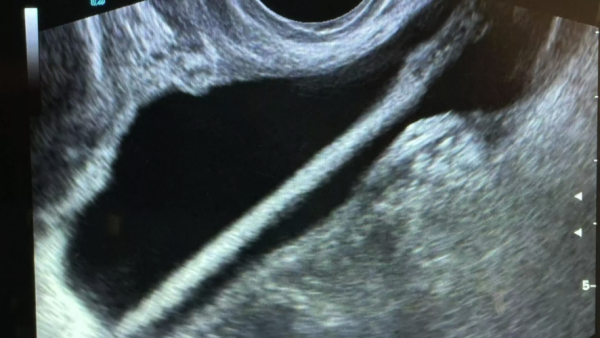

Сначала медики провели УЗИ, а после операцию, во время которой они вытащили карандаш. Все прошло успешно и без осложнений. Женщину уже отпустили домой.